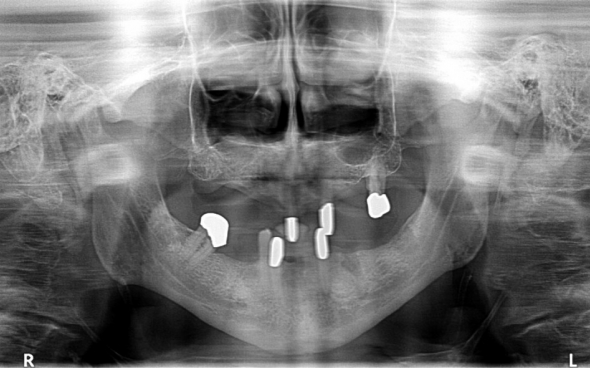

Der 75 jährige deutsche Patient machte sich mit einem Lückengebiss und einem herausnehmbaren Zahnersatz in schlechtem Zustand vorstellig. Mehrere Zähne mussten extrahiert werden.